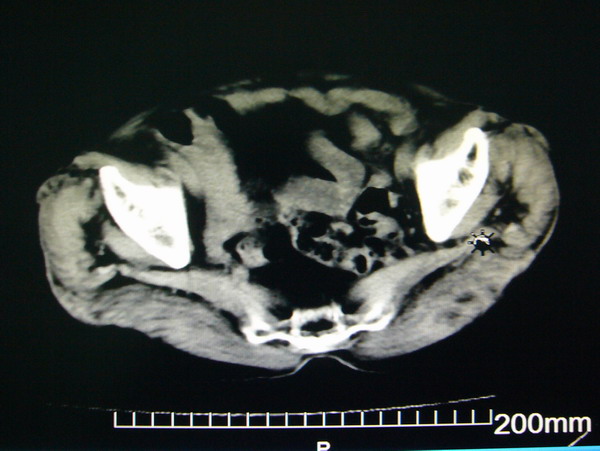

女:83y,转移性右下腹痛2小时,白细胞计数增高。

1.右侧肾盂扩大,肾盏无扩张,考虑:先天性肾盂变异可能性大。

2.胆囊扩张,考虑:胆囊炎。

3.阑尾区域可见以结节样高密度影,结合病史,考虑:阑尾结石,阑尾炎。

右下腹肠系膜增厚,结合病史支持阑尾炎.

右侧壶腹型肾盂可能,建议输路造影或增强

1.右侧肾盂扩大,考虑先天性肾盂变异或肾盂旁囊肿。

2.胆囊扩张,考虑胆囊炎。

3.阑尾区域可见结节样高密度影,结合病史考虑:阑尾结石、阑尾炎。